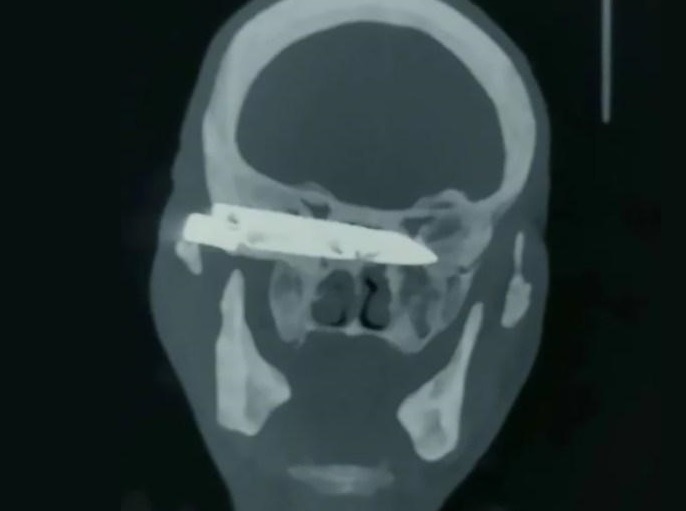

【画像】強盗に、頭にナイフを突き刺された40代男性「まぁいっか…」 ⇒ 26年後

gif_animation 中国にて驚愕のニュース。頭痛、視力障害を訴え病院を受診した70歳男性の頭の中から、「44歳時に強盗に襲われ突き刺されたものの、ずっと放置していたナイフ」が摘出されたとの事。26年ぶりに外に出る事ができたナイフ。一連の画像。[3]images